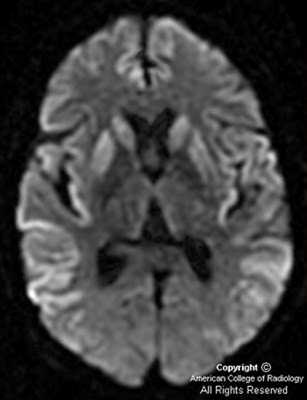

На диффузионно-взвешенной (DWI) магнитно-резонансной томографии (МРТ) головного мозга выявляются аномальные билатеральные гиперинтенсивные сигналы на Т2-взвешенных изображениях (симптом «медовых сот») преимущественно в области головок хвостатых ядер, таламуса, отмечается атрофия коры больших полушарий и мозжечка [6].

При проведении МРТ головного мозга в Т2-режиме определяется так называемый «симптом медовых сот» - участки повышенного сигнала, исходящие от подкорковых ганглиев и таламуса. Зачастую выявляются признаки атрофических изменений мозжечка и коры головного мозга, расширение желудочков и боковых цистерн мозга. ПЭТ диагностирует зоны пониженного метаболизма, локализующиеся в подкорковых ядрах, полушариях мозжечка и коре мозга.

До недавнего времени «золотым стандартом» верификации диагноза БКЯ являлась биопсия головного мозга, позволяющая выявить характерные изменения в мозговой ткани в виде мелких вакуолей в телах нейронов, из-за чего ткань мозга приобретает губчатый вид, пролиферации клеток глии при отсутствии признаков воспаления. При электронной микроскопии возможно обнаружение прионных палочек, являющихся патогномоничным признаком заболевания. Указанные морфологические изменения отмечаются в коре головного мозга, базальных ганглиях, мозжечке и верхних отделах ствола мозга. Однако в случаях БКЯ биопсия мозга не нашла широкого применения в клинической практике из-за инвазивности метода, сложности санитарной обработки оборудования и утилизации биоматериалов, связанных с высокой устойчивостью прионов, а также вследствие небольшого объема биоптата мозговой ткани, что может быть причиной ложноотрицательных результатов морфологического и иммуногистохимического исследования. Однако в настоящее все больше распространена МРТ диагностика данного заболевания, по причине выявления специфических изменений, наиболее информативными являются последовательность DWI.

Постановка окончательного прижизненного клинического диагноза стала возможной после генетического анализа в целях выявления мутации в 129-м кодоне гена прионного белка 20-й хромосомы и выявленных изменений на МРТ DWI-томограммах головного мозга в виде аномального свечения хвостатого ядра и скорлупы.

- На МРТ можно выявить признаки атрофических изменений в мозжечке и коре мозга (синдром «медовых сот»), расширение желудочков. От подкорковых структур и таламуса иногда улавливаются участки с повышенным сигналом.